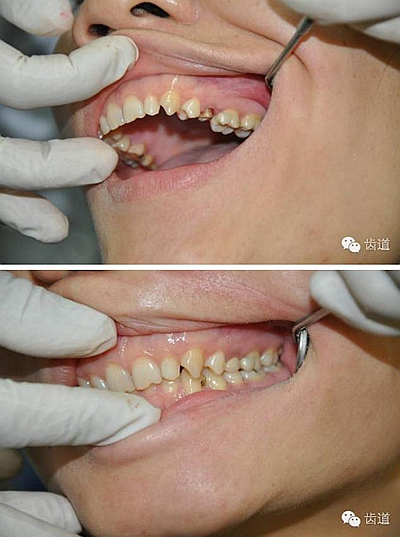

如果肩臺制備不到位或不制備肩臺,全冠戴入后冠邊緣就會形成異物懸突,刺激牙齦,引起齦發(fā)炎出血,時間一長甚至?xí)?dǎo)致牙冠腐爛。

內(nèi)冠邊緣懸突是導(dǎo)致牙齦變色的"罪魁禍?zhǔn)?quot;

肩臺懸突易出現(xiàn)繼發(fā)齲